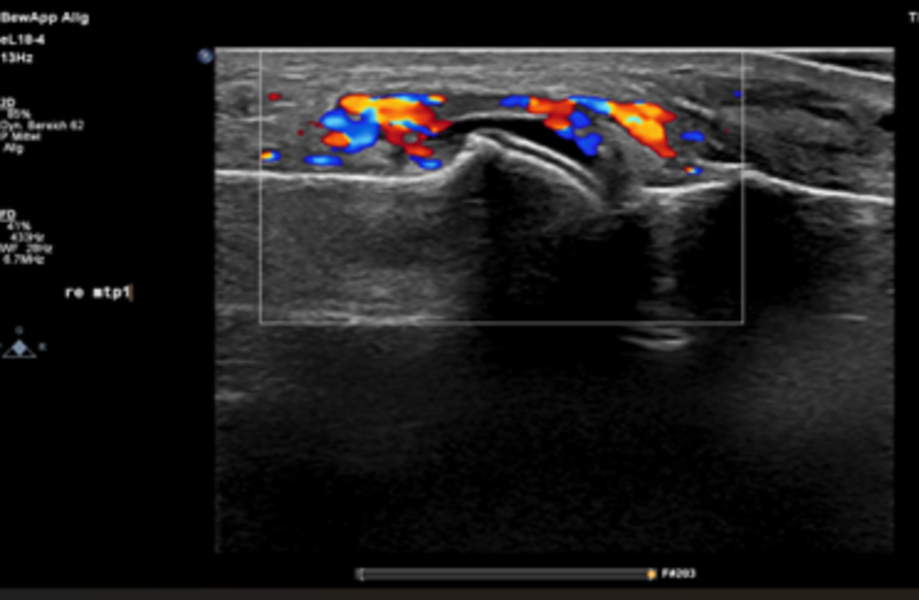

Gelenksonographie und Gelenkpunktion

Die Gelenkpunktion ist ein häufig angewendetes Verfahren, das sowohl zur Diagnostik als auch zur Behandlung von Gelenkbeschwerden eingesetzt wird, insbesondere bei Schwellung oder Schmerzen durch einen Gelenkerguss. Dabei wird unter sterilen Bedingungen mit einer feinen Nadel Flüssigkeit aus dem Gelenk entnommen, was meist nur kurz unangenehm ist. Die gewonnene Gelenkflüssigkeit wird im Labor untersucht, um die Ursache der Beschwerden zu klären, z. B. ob eine Entzündung, eine Infektion oder eine Kristallerkrankung wie Gicht vorliegt. Gleichzeitig kann die Entlastung des Gelenks oft schon zu einer deutlichen Linderung der Schmerzen führen, zusätzlich kann ein entzündungshemmendes Medikament direkt in das Gelenk eingebracht werden.

Die Gelenksonographie ist heute ein etabliertes Verfahren zur Detektion von Gelenkergüssen, Synovitis sowie Enthesitiden und ist in unserem klinischen Alltag fest in der rheumatologischen Sprechstunde implementiert. Sie hilft, Entzündungen sichtbar zu machen, die Punktion gezielt durchzuführen und kann auch typische Veränderungen bei Gicht darstellen, wodurch die Diagnose unterstützt wird.